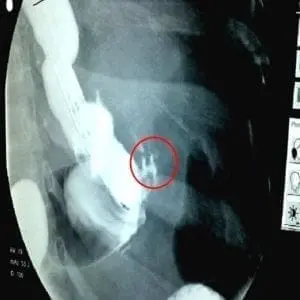

- Upper GI

Esophagram showing leak after gastric sleeve

Upper GI’s are xrays that are done under live fluoroscopy while the patient swallows some contrast dye. The contrast dye shows up as white on an xray. In the xray above the sleeve is the long column of white dye that heads up towards the upper left corner of the xray. You can see a small amount of dye within the red circle, that is outside of the sleeve. This indicates a leak.